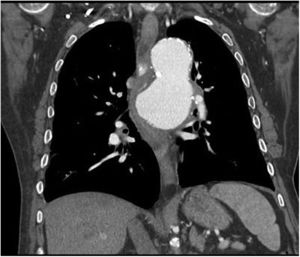

Varón de 64 años con antecedentes de aneurisma de aorta torácica que acude a urgencias por sensación de stop a nivel de esófago medio que condiciona vómitos tras la ingesta negando impactación alimentaria. Refiere en los últimos vómitos presencia de hebras de sangre, además de disnea y ortopnea. En la radiografía de tórax se visualiza aumento de tamaño del aneurisma de aorta, por lo que se realiza angio-TC observando contenido hiperdenso en la luz esofágica, así como signos de inestabilidad y úlcera penetrante que contacta y comprime la luz esofágica y el bronquio izquierdo (figs. 1 y 2). Se realiza cirugía urgente con colocación de endoprótesis aórtica sin complicaciones inmediatas. A las 48h el paciente presenta hematemesis observando en gastroscopia coágulo en esófago medio y sangrado pulsátil. Ante la sospecha de endoleak se realiza revisión quirúrgica con arteriografía que no muestra fuga periprotésica. El paciente presenta shock hemodinámico que no responde a politransfusión y fármacos vasoactivos produciéndose éxitus. En la autopsia se confirma la presencia de fístula aortoesofágica (fig. 3).